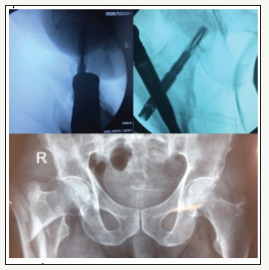

Total number of patients were 83. about 49 women and 34 man. After one year we assessed mortality rate As we got, 24% (20 patients) mortality rate after one year and 6% (3 man and 2 women) death in first month. Of this number (20 patients) 12 were women (14.4%) and 8 were man (9.6%) (Figure 1-4).

Figure 1:OTA/31A3.

Figure 4:OTA/31A3.